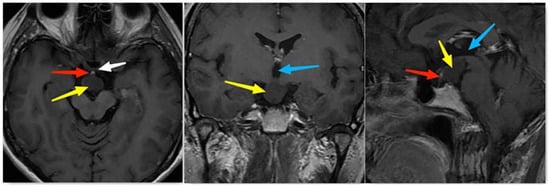

2. Patient Information

| ShaoGuang Li et al. | 40, F | Dizziness, visual field defect | NR | Suprasellar | Enhanced 1.7 × 1.1 cm cystic mass | GTR + R | Craniopharyngioma |